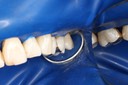

Chris Woo #18 prep